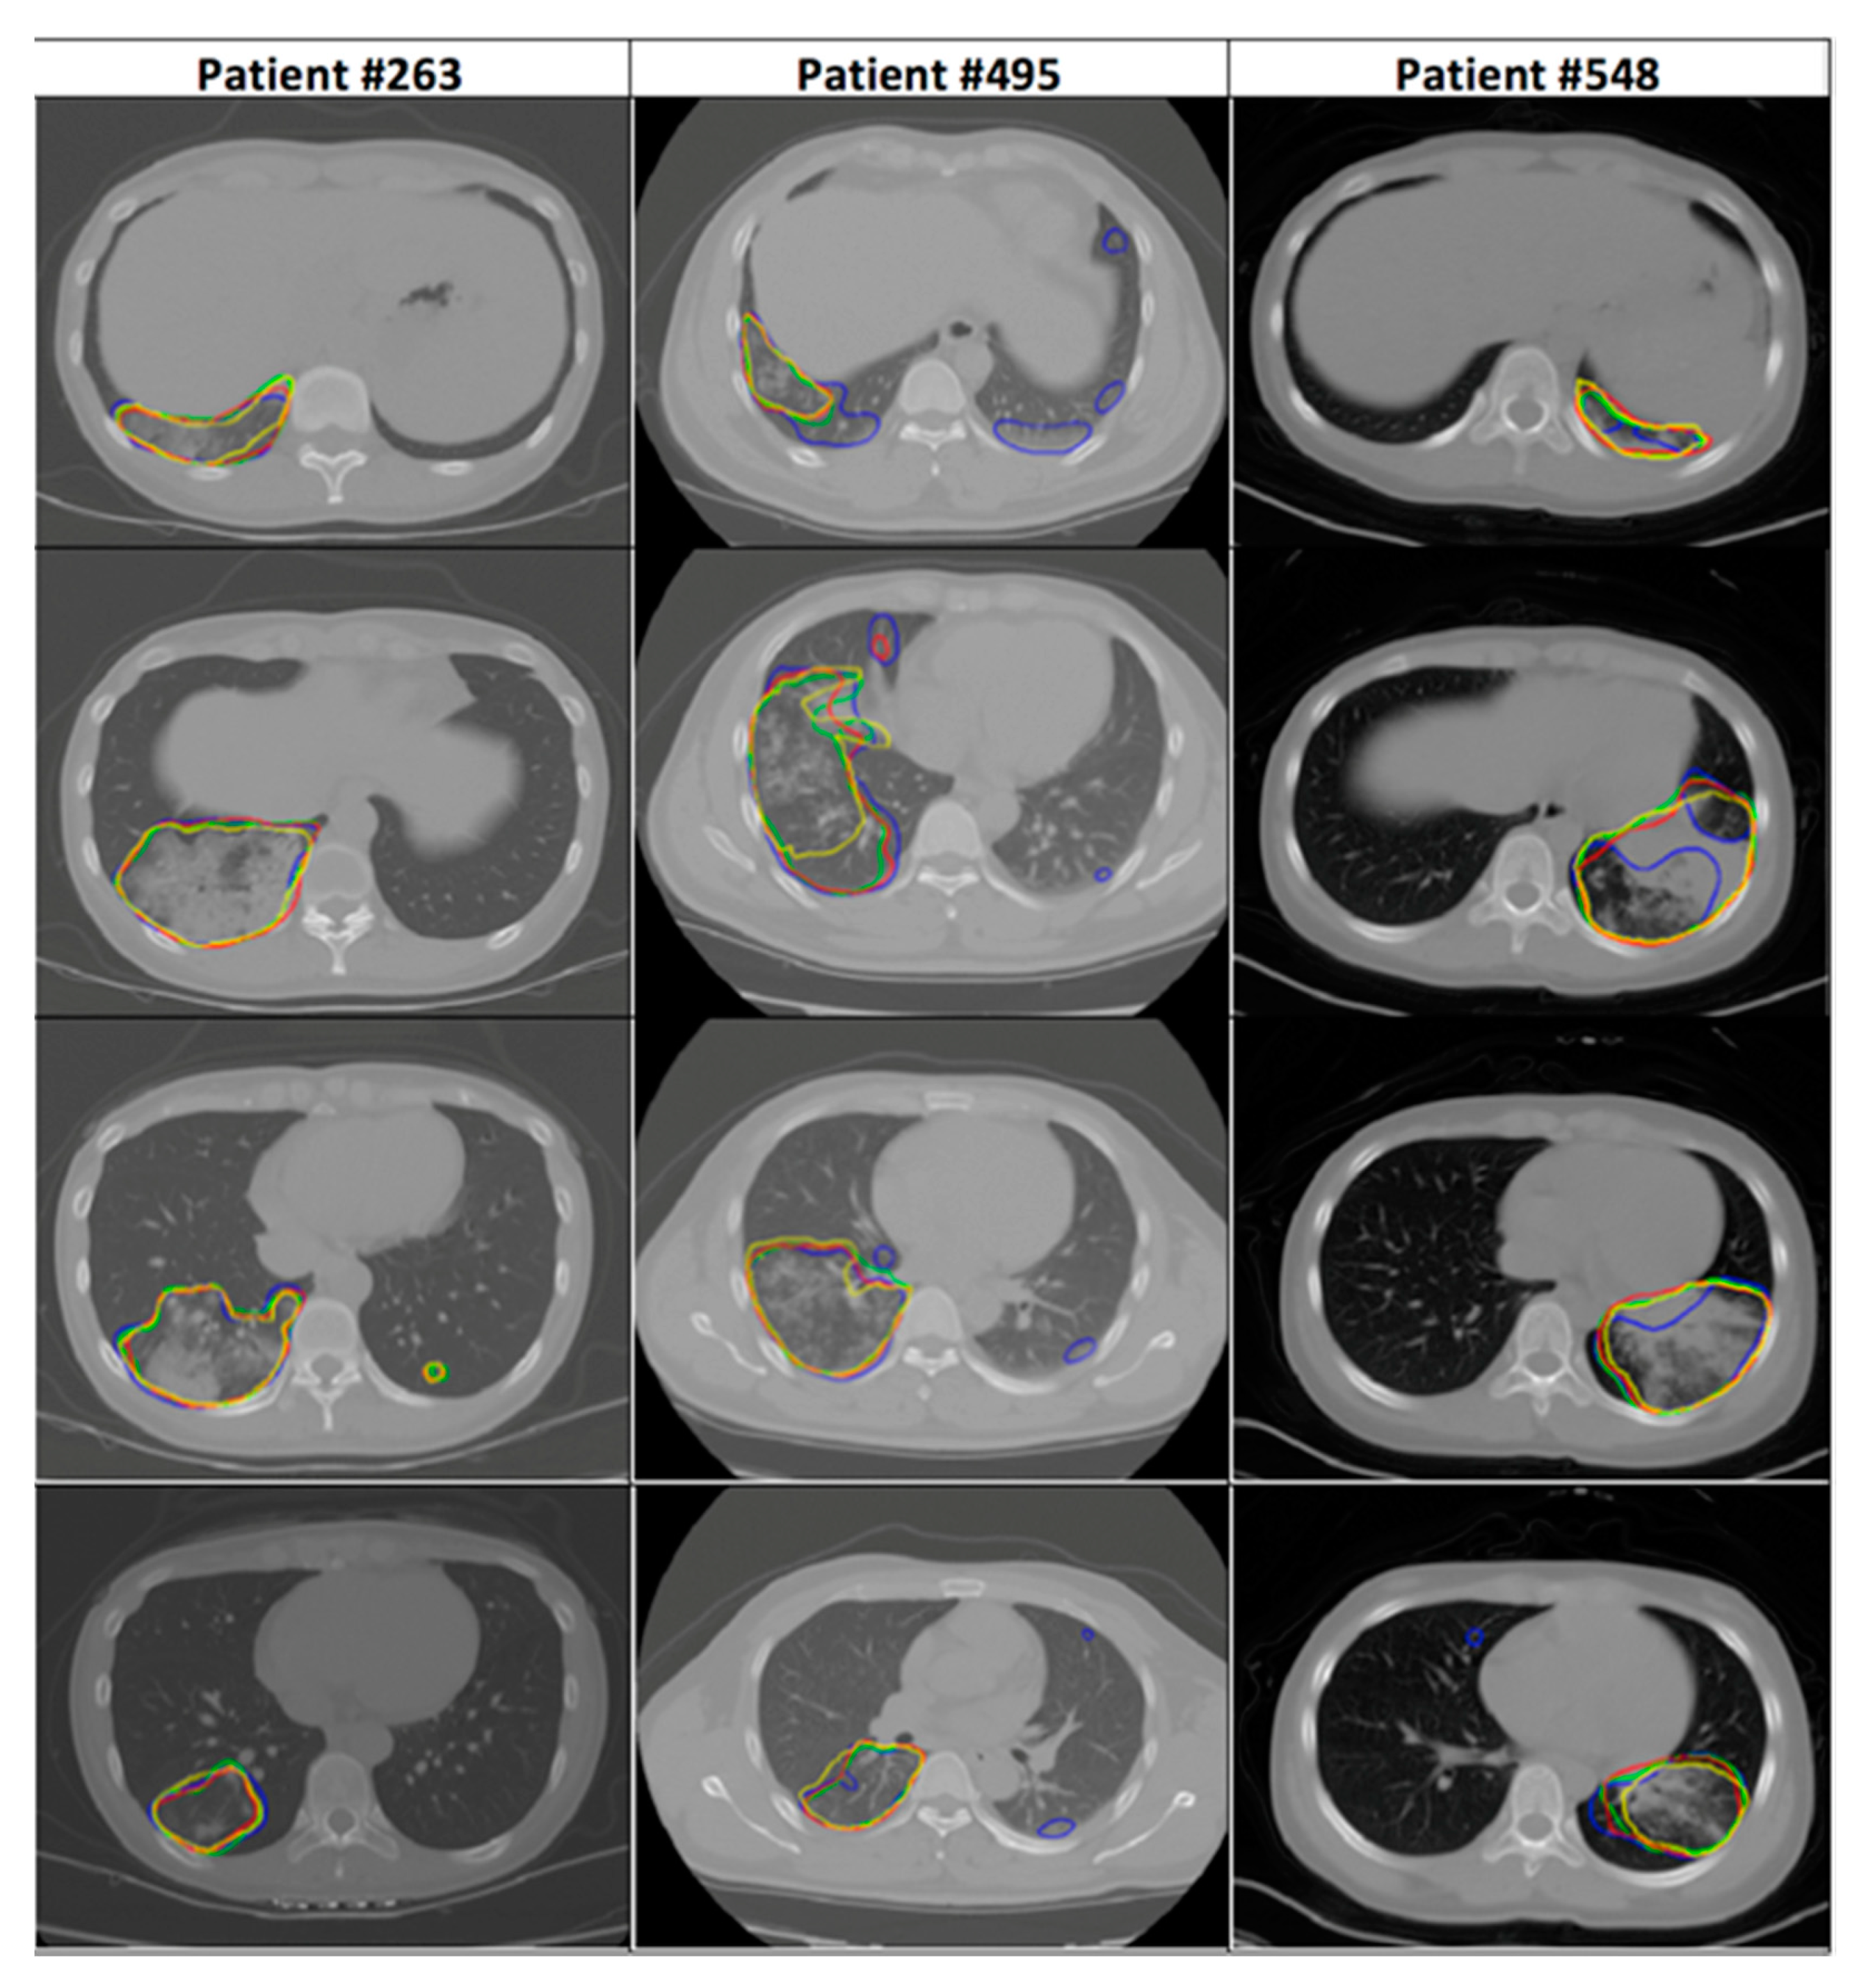

2.1. Dataset